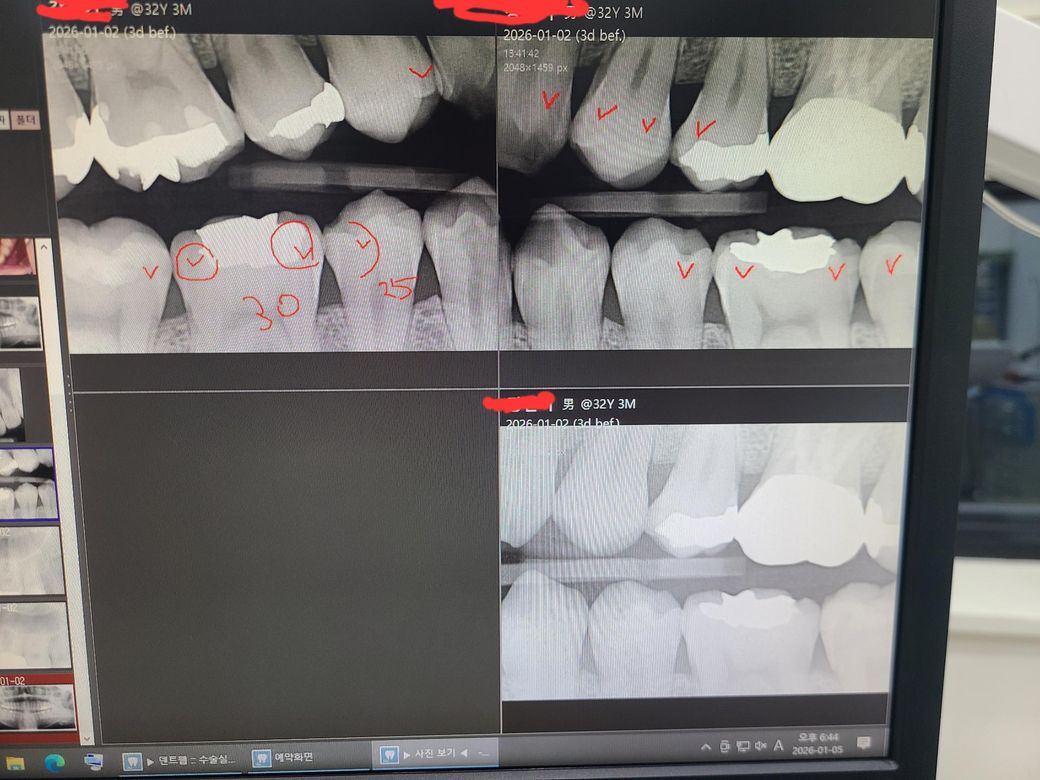

교익 촬영 했는데 한번만 봐주시면 감사드리겠습니다

총 9군데에 인접면 충치가 있다고 진단 받았고

전체 다 레진 충전으로 치료를 하신다고 하십니다

가격은 치아당 충치 1개면 25, 2개면 30 말씀하시는데

실제 정말 다 수술을 받아야되는건지 한번만 봐주시면 감사드리겠습니다

• 1번 째 사진

엑스레이 상으로 치아 사이에 충치가 있어 보이긴 하지만, 관리를 하면서 지켜볼수도 잇을것같습니다.

3. 엑스레이에서 일부 인접면 충치가 관찰되긴 합니다